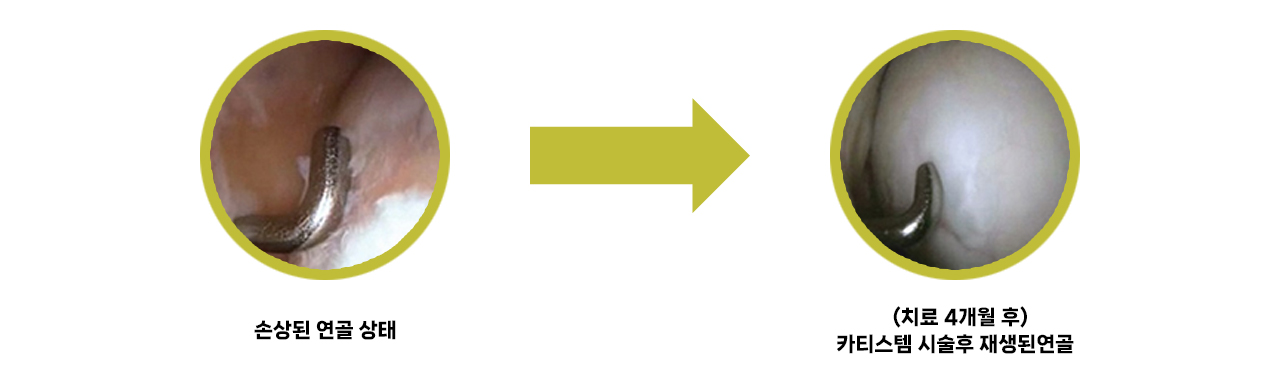

관절줄기세포 시술

관절내시경이나 최소절개를 하여, 제대혈유래 줄기세포 치료제(카티스템)를 도포하여 치료

치료 사례

제대혈 유래 줄기세포 치료의 장점

- 모든 연령층에서 연골재생효과를 누릴 수 있음

- 1회의 치료만으로도 탁월한 연골재생효과를 기대할 수 있음(개인차 있을 수 있음)

- 연골결손 크기가 큰 경우에도 연골 재생효과가 뛰어남